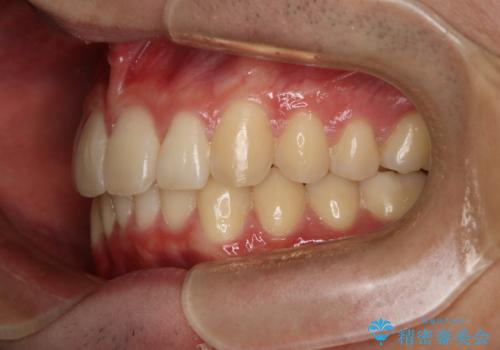

- 口元の突出感は気にならないが、上の前歯の角度と、下の前歯のがたつきが気になるとご相談にいらした方です。なるべく費用や治療期間を抑えて治療したいとのご希望に合わせて治療を計画しました。

この患者様への治療方針として、奥歯から少しずつ歯を移動させる方法と、歯をわずかに削って並べる方法とをご提案しました。短期間での治療を望まれたため、歯をサイズダウンさせて歯を並べました。わずかではあるものの、削った歯は元には戻せないことを十分ご説明し、ご理解ご了承を頂いた上で治療を行いました。